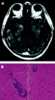

Vascular cuffing